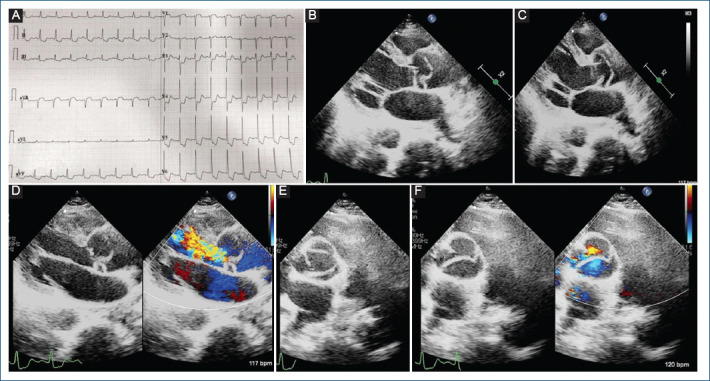

Look before you leap! - A case report of left main dissection causing myocardial infarction.